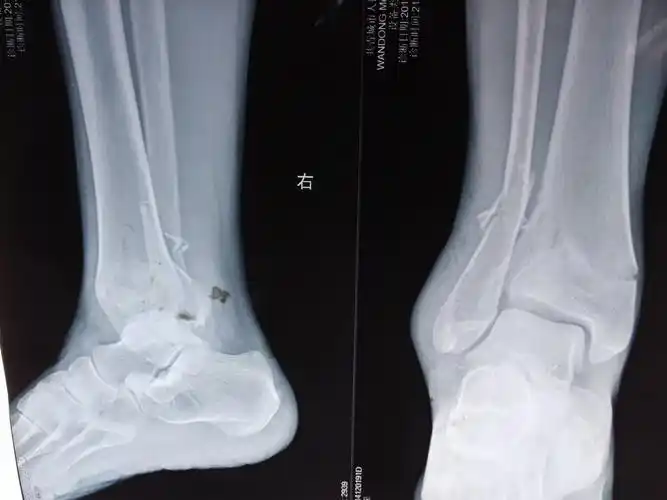

一例胫腓骨远端骨折下胫腓联合分离病例